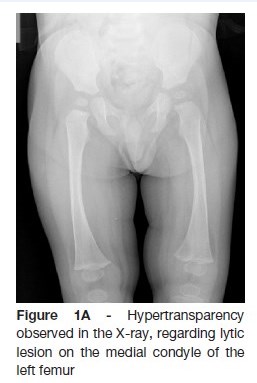

The radiography showed a lytic lesion on the medial femoral condyle (Figure 1A) which was later confirmed by computed tomography and magnetic resonance (Figure 1B).

A previously healthy 12-month-old boy, was observed in the emergency department due to refusal to walk, initially diagnosed as transient synovitis of the hip. After one month, he is again observed due to the persistence of symptoms and fever. On objective examination he presented refusal to walk, reporting no difficulties in crawling. A conventional radiography showed lytic lesion on the medial condyle of the left femur and computed tomography (CT) revealed a probable Brodie abscess. Patient was referred to pediatric orthopedics consultation and then performed a magnetic ressonance that confirmed osteomyelitis with an intraosseous abscess. He was submitted to surgical drainage and four weeks of antibiotic therapy, with no sequelae after one year.